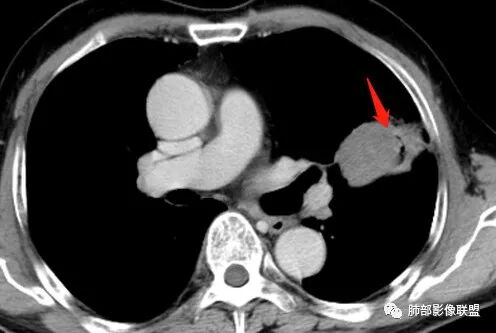

这三个月后的

发了后面这个,就不用纠结了,直接秒了。

大雄:

我只是要告诉大家,不是二元,就是肿瘤,没有什么感染,磨玻璃都没消失。